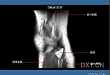

2016.04.06 高清图解:磁共振下的膝关节

不同层面的膝关节 MRI 图像,骨骼、肌肉、韧带等一览无遗。